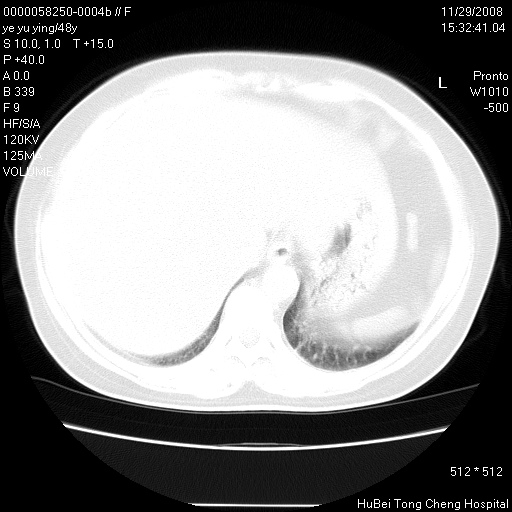

以下是引用zsl6918在2008-11-29 21:47:00的发言:[br]恶性肿瘤病史,转移瘤首先考虑。脂肪肝,胆囊结石。

以下是引用huenhao在2008-11-29 22:11:00的发言:[br]脂肪肝,胆囊结石。左肺病灶建议定期复查。

以下是引用liuyue在2008-11-30 5:44:00的发言:[br]1.左肺病变,首先考虑感染性病变,转移待排;建议治疗后复查。[br]2.肝脏密度普遍减低,考虑与化疗有关。[br]3.胆囊结石.